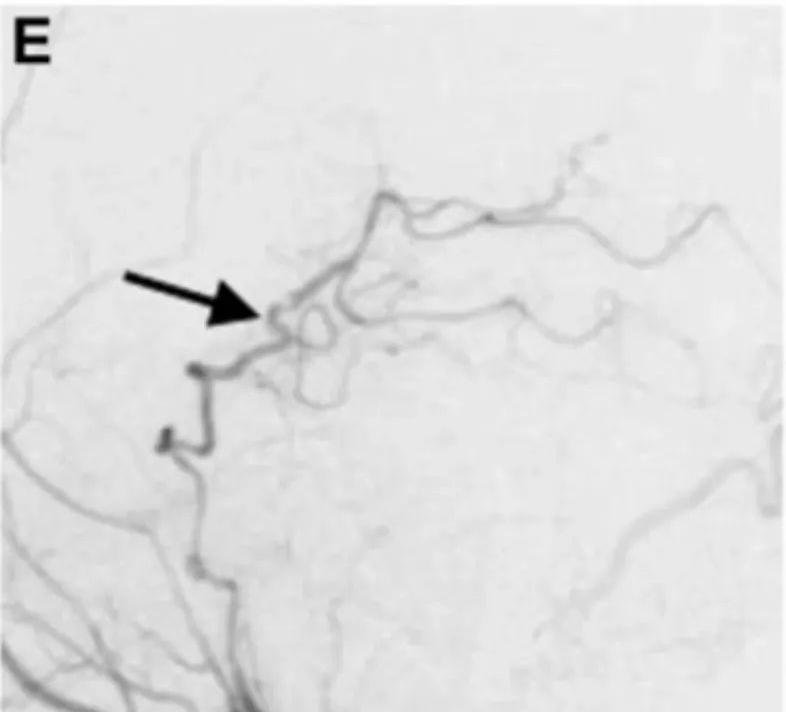

术后阶段

- 术后第1天,DSA显示左侧PCA区域血流灌注显著改善,动脉瘤完全隔绝无残留显影。

- 术后2周,患者神经功能完全恢复出院。

- 12个月随访,改良Rankin评分0分,证实搭桥血管长期通畅。